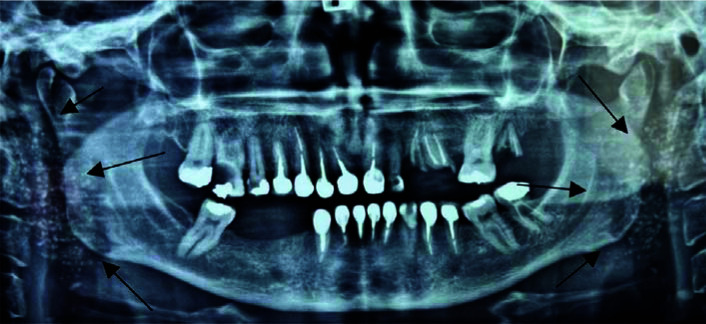

This study investigates the calcifications in the parotid glands of a patient with Sjögren's syndrome (SS). A 52-year-old female patient presented for a routine dental examination who found to have multiple radiopacities in both parotid glands on panoramic radiograph. Further evaluation revealed swelling and tenderness in the parotid glands, decayed teeth, and dryness of the mouth and eyes. Ultrasound examination showed enlarged parotid glands with heterogeneous echogenicity, hypoechoic and cystic foci, and multiple calcifications. Laboratory tests indicated positive findings for rheumatoid factor and anti-SSA/SSB antibodies, consistent with a diagnosis of Sjögren's syndrome. Treatment primarily focuses on relieving symptoms and preventing clinical manifestations.